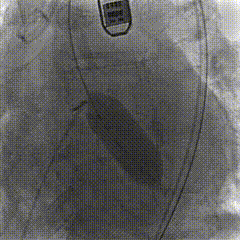

主动脉根部造影

18mm球囊预扩,无腰,造影剂轻微渗漏

瓣膜释放至工作体位,一次成功

瓣膜形态位置良好,冠脉灌注良好